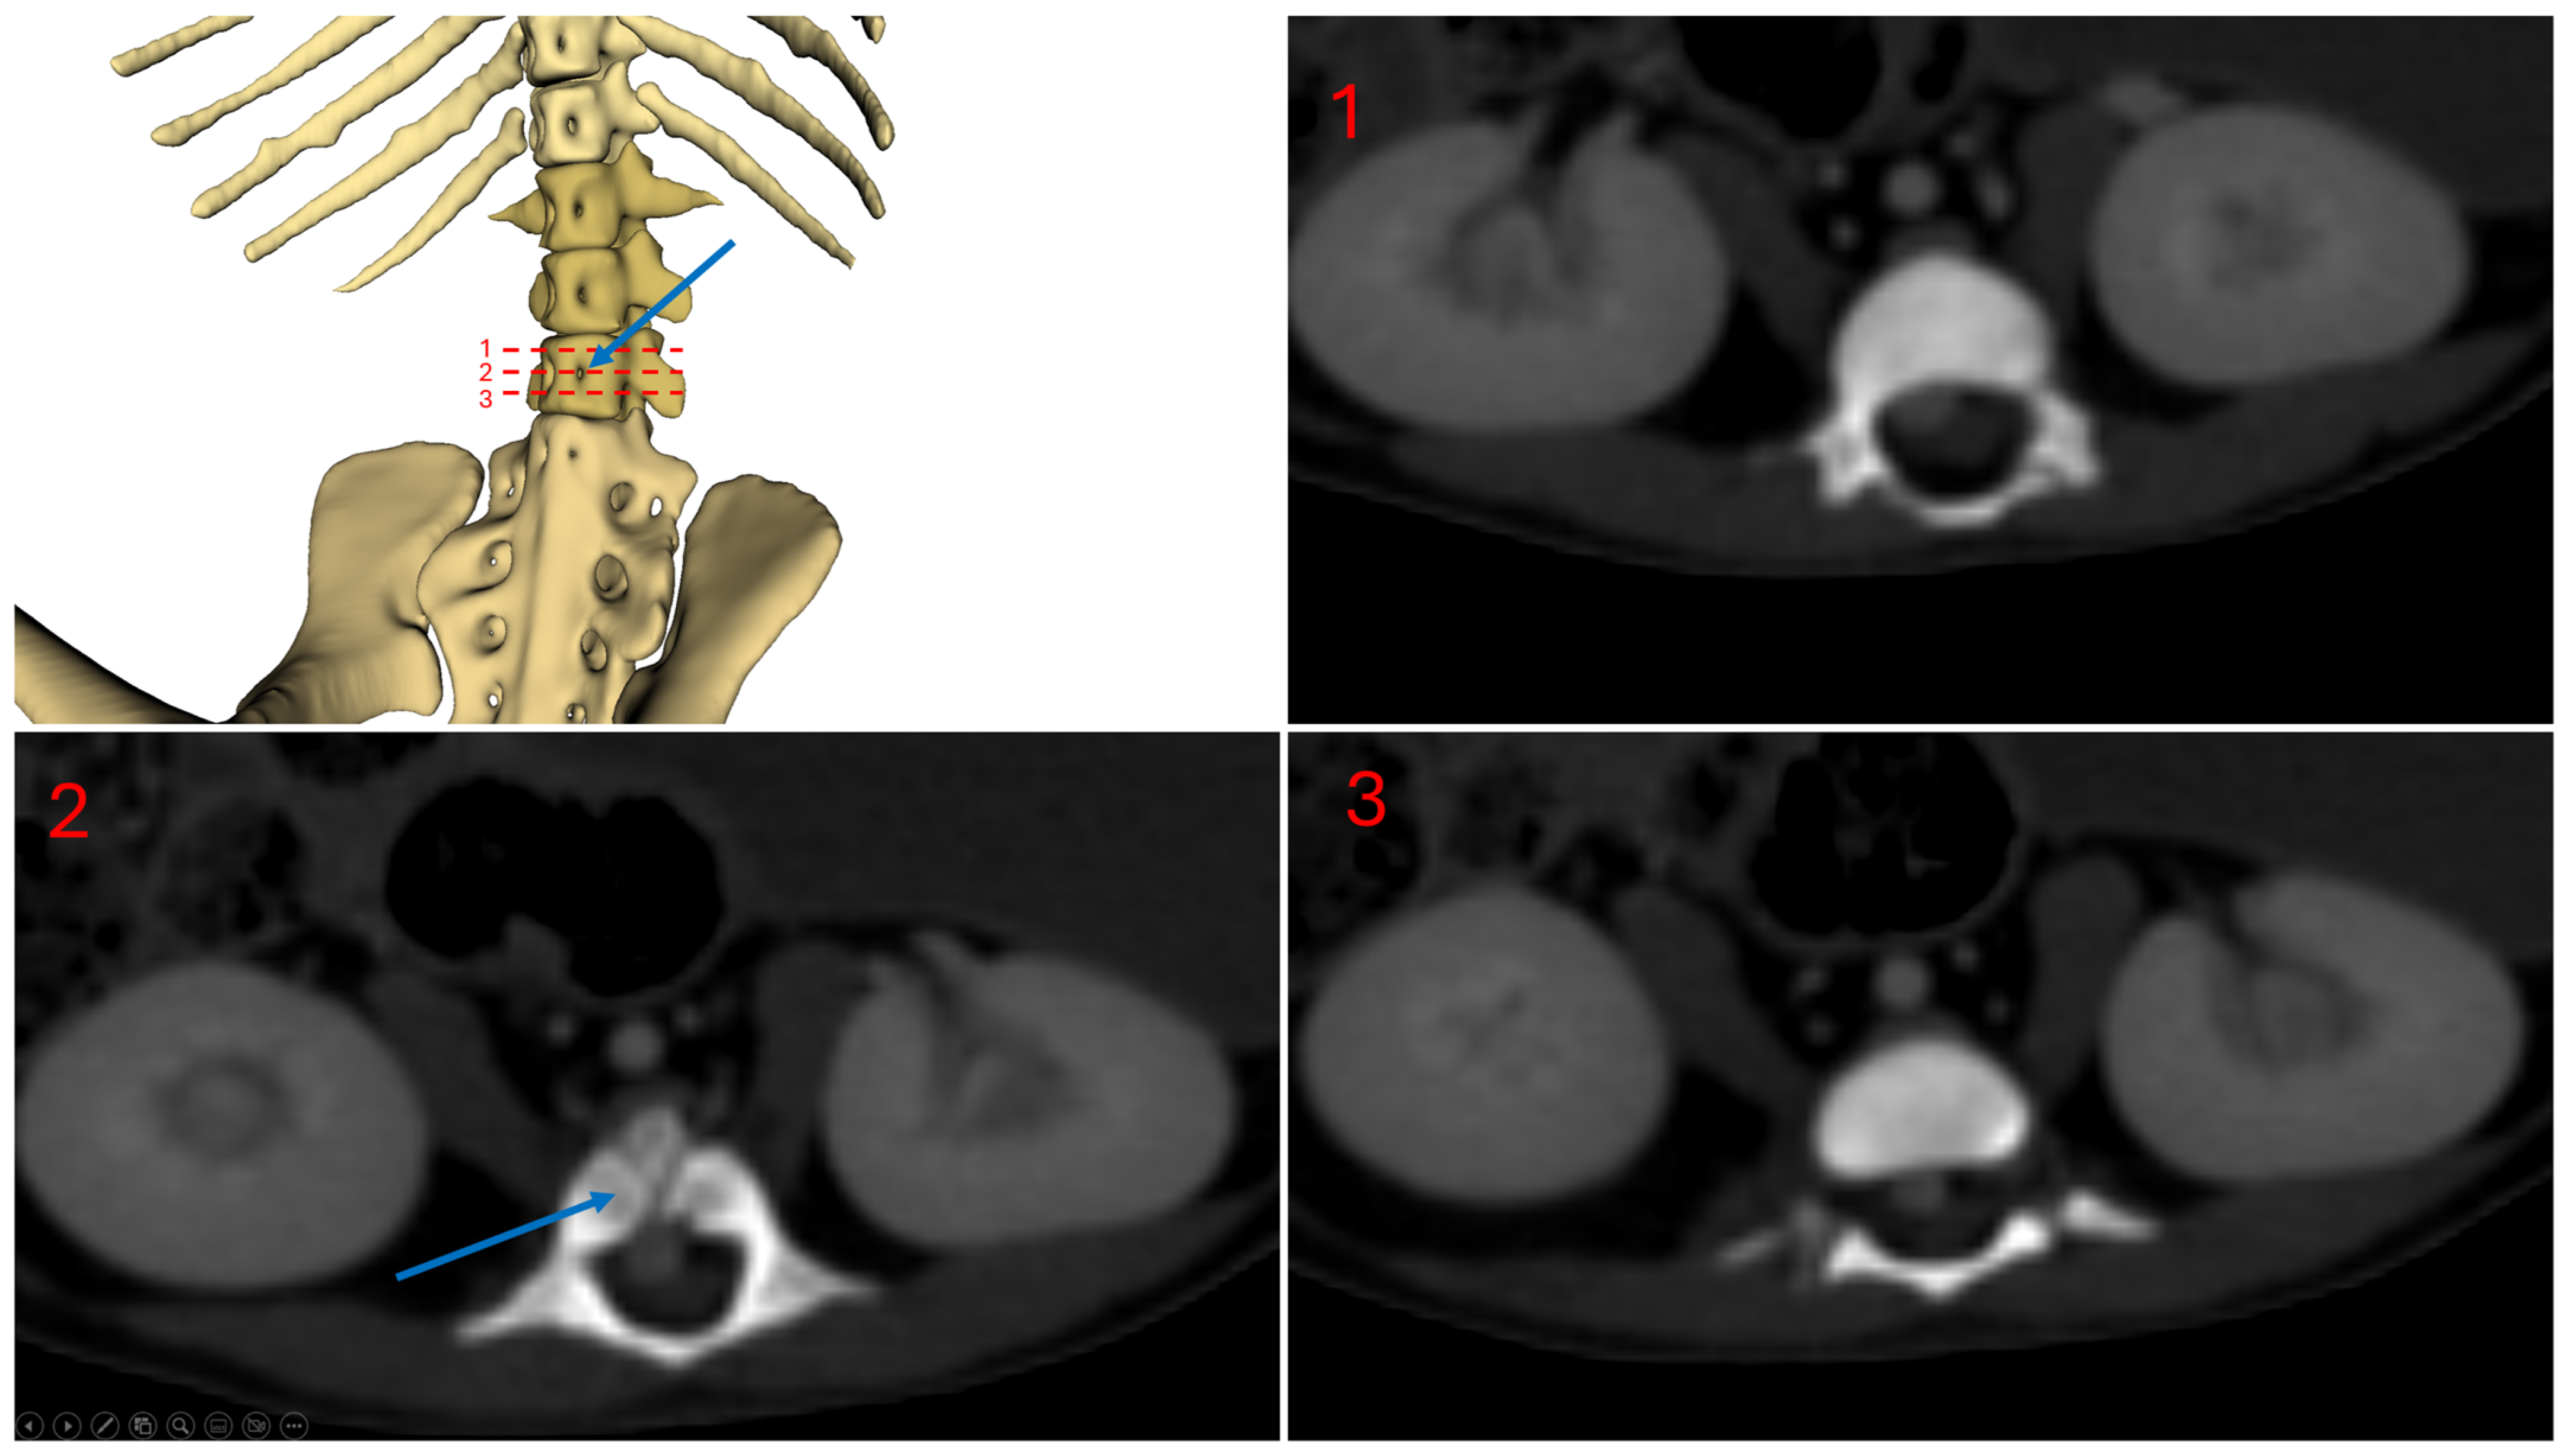

Figure 5 shows a ventral view of subject 1, highlighting the vertebral foramina. The blue arrow indicates the vertebral foramina located on the third lumbar vertebra.

Figure 5.

Subject 1 vertebral foramina, L3 level.

3.1. Subject 1

In the first subject, we observed the presence of a venous network originating from the kidneys, at the level of the 3rd lumbar vertebra, converging at the 23rd thoracic vertebra, and continuing its path cranially up to the 18th thoracic vertebra, to the right side of the spine, before terminating (Figure 2 and Figure 3).

This double caudal vena cava communicated with the intravertebral vein through several basivertebral veins, entering through the vertebral foramina (Figure 4 and Figure 5).

A significant part of the venous flow entered the intravertebral foramen through the second ventral sacral foramen, after receiving the veins from the pelvic limbs (Figure 2, Figure 3, Figure 4 and Figure 5).

This subject did not exhibit any visible communication between the pre-hepatic segment of the caudal double vena cava and the post-hepatic segment of the caudal vena cava draining the supra-hepatic veins (Figure 2 and Figure 3).

After entering the vertebral canal through the first and second ventral sacral foramen and vertebral foramina, the venous flow traveled in the right part of the vertebral canal, to the right of the spinal cord, and then described an anastomotic arch around the ninth right rib, and directly drained into the cranial vena cava, via the arch of the azygos vein (Figure 3)

The right atrium received the post-hepatic segment of the caudal vena cava caudally. Cranially, it received the confluence between the cranial vena cava and the arch of the azygos vein, which itself received the intravertebral vein (Figure 3).